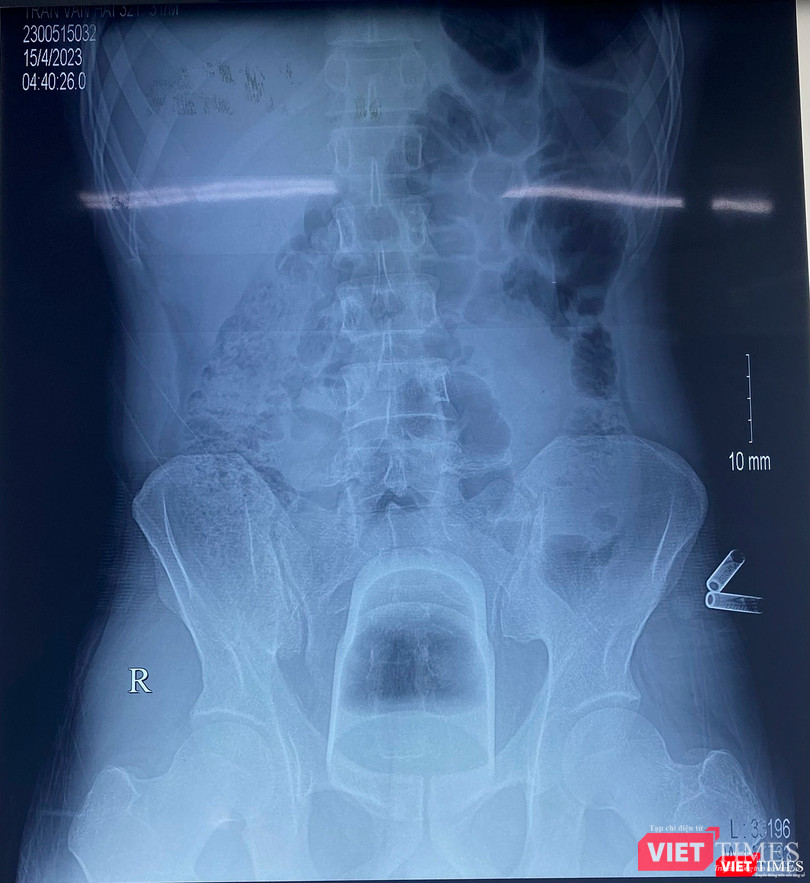

"Kết quả phim chụp X-quang phát hiện dị vật nằm sâu trong trực tràng của bệnh nhân. Do dị vật có kích thước lớn, lại nằm rất sâu trong trực tràng và kẹt chặt vào khung chậu nên không thể lấy được qua đường hậu môn. Các bác sĩ quyết định mổ mở trực tràng để lấy dị vật và đưa đại tràng sigma ra ngoài làm hậu môn nhân tạo”- BS Phạm Hiếu Tâm cho biết.

Phim X-quang chiếc cốc đánh răng nằm sâu trong trực tràng của bệnh nhân (ảnh BVCC) |